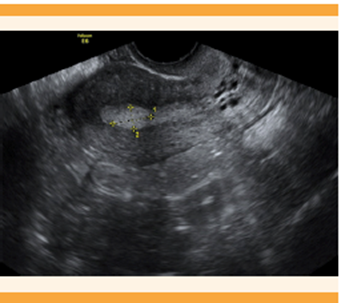

Los pólipos endometriales son protrusiones benignas del endometrio conformadas por un componente vascular, glándulas y estroma, que pueden variar en cantidad, textura y tamaño que puede ir desde milímetros hasta varios centímetros (Figura 4). 13 Los factores de riesgo descritos para los pólipos endometriales son: la edad, hipertensión, obesidad y tratamientos con tamoxifeno. 14 Por lo general, son asintomáticos, pero en algunas pacientes pueden ser la causa de sangrado uterino anormal. 15

Figura 4 Imagen ecográfica de una paciente de 30 años con sangrado uterino anormal consistente en manchado intermenstrual, se evidencia un pólipo endometrial de 12 x 7 mm.